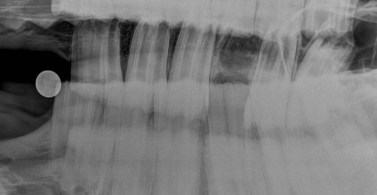

Dental disorders

Radiographic changes consistent with periapical infection are most readily identified in the rostral maxillary equine cheek teeth whose apices lie rostral to the maxillary sinuses, and the mandibular cheek teeth, whose apices are contained within the mandible.9 In the more caudally positioned maxillary cheek teeth where secondary dental sinusitis is common, apical infections can be recognized with confidence in only 50–57 % of cases using radiography alone.9,12 Two more recent studies by Weller et al and Barakzai that have investigated the accuracy of radiography for diagnosis of equine dental disorders found radiographic sensitivities of 52 % and 69 % (respectively) and specificities of 95 % and 70 %.13,14 The differences between the results of these two studies are likely to be attributable to the different anatomical distribution of disorders in the two studies, with a considerably higher proportion of cases with dental sinusitis in the latter study as compared to predominantly mandibular or rostral maxillary dental lesions in the study performed by Weller et al (2001).13 A further study, using computed radiography,10 reported that periapical sclerosis, periapical lucency, and clubbing of tooth roots are the most reliable radiographic changes associated with periapical infection, but that mild changes in any of these categories are not dependable indicators of infection. This study also reported that loss of the lamina dura denta is a very insensitive (high number of false positives), but highly specific (low number of false negatives) indicator of periapical infection.